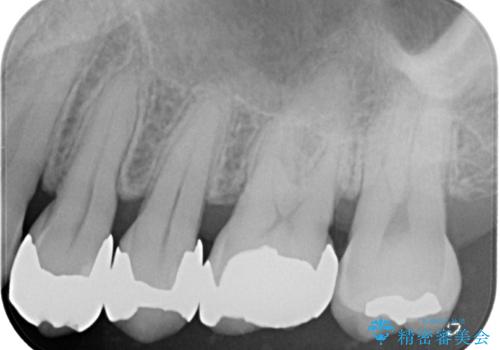

- 治療計画

- 当院で矯正後徐々にセラミックにやり替えたいとのことで来院された患者様です。レントゲン撮影の結果、メタルインレーの不適合を認めました。またメタルインレーの範囲も大きくご自身の残せる歯の量を考慮してオールセラミッククラウンによる補綴治療を行っていくことにしました。